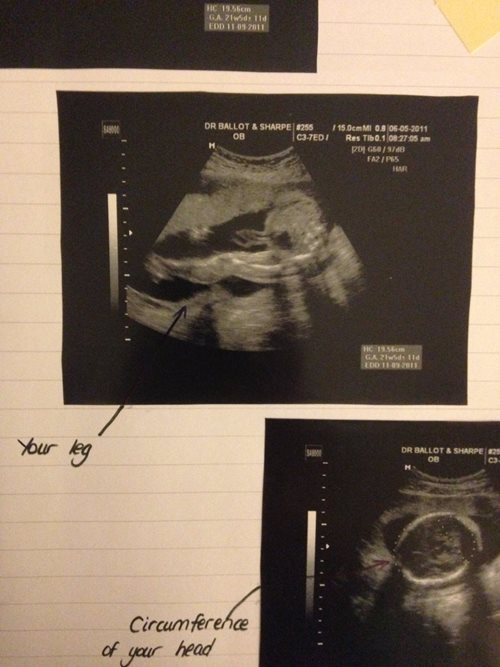

I had scans regularly, more than most Mamas. I ate as healthily as I could. I saw a therapist every week with the instruction “I’m having a baby in a few months… Get me ready”! I kept busy and surrounded myself with positive and supportive people. I wrote a journal and I spent a lot of time thinking. I attended pre-natal classes with my own Mama in the evenings leading up to the birth. My childhood dog passed away and my brother’s lung collapsed during that time too, so it was a heavy year.